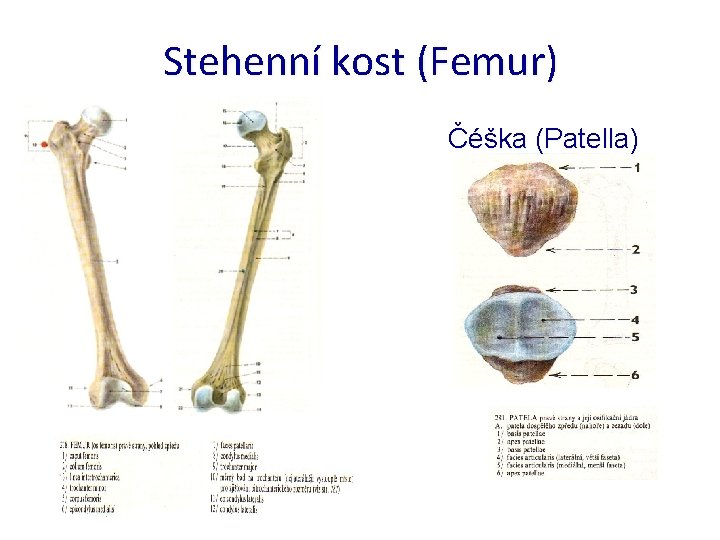

Stehenní kost (Femur) Čéška (Patella)